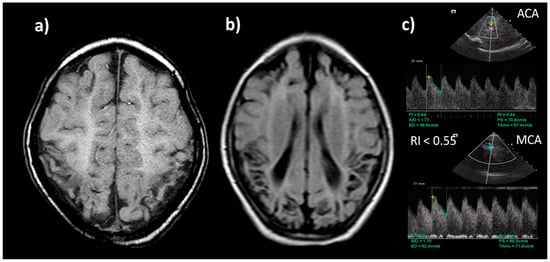

8.6. Neuroimaging

- Archer, L.N.; Levene, M.; Evans, D. Cerebral artery doppler ultrasonography for prediction of outcome after perinatal asphyxia. Lancet 1986, 328, 1116–1118. [Google Scholar] [CrossRef]

- Bednarek, N.; Mathur, A.; Inder, T.; Wilkinson, J.; Neil, J.; Shimony, J. Impact of therapeutic hypothermia on MRI diffusion changes in neonatal encephalopathy. Neurology 2012, 78, 1420–1427. [Google Scholar] [CrossRef] [PubMed]

- Trivedi, S.B.; Vesoulis, Z.A.; Rao, R.; Liao, S.M.; Shimony, J.S.; McKinstry, R.C.; Mathur, A.M. A validated clinical MRI injury scoring system in neonatal hypoxic-ischemic encephalopathy. Pediatr. Radiol. 2017, 47, 1491–1499. [Google Scholar] [CrossRef] [PubMed]

- Groenendaal, F.; De Vries, L.S. Fifty years of brain imaging in neonatal encephalopathy following perinatal asphyxia. Pediatr. Res. 2017, 81, 150–155. [Google Scholar] [CrossRef] [PubMed]